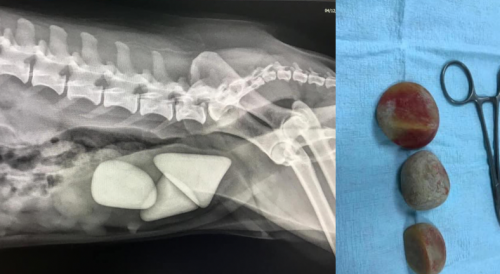

RADIOLOGIA